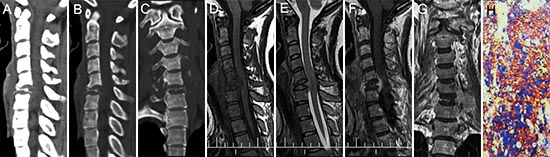

Figure 6: pPNET in a 26-year-old woman. CT imaging showed compression fractures in the 6th cervical vertebra (A-C). Precontrast MRI showed an irregular mass around the compressed 6th cervical vertebra that was iso-intense on T1WI (D) and iso-intense on T2WI (E). Contrast MRI showed the mass had significant enhancement (F). Coronal images of the enhanced MRI showed invasion into the paraspinal soft tissues (G). The poorly differentiated small round tumor cells were CD99 positive (H × 100).

Figure 2: pPNET in a 21-year-old man. Precontrast CT images showed a lobular iso-dense mass with necrosis in the left retroperitoneum (A). Enhanced CT images showed the mass had heterogeneous contrast uptake (B-C). Precontrast MRI showed the mass had an ill-defined border that was iso-intense on T1WI (D) and hyper-intense on T2WI (E). Contrast MRI showed the mass had significant and heterogeneous enhancement (F). Sagittal enhanced MRI images showed the mass invaded the 5th lumbar vertebrae and spinal canal (G). The small round tumor cells were positive for CD-99 (H × 100).

Figure 3: pPNET in an 11-year-old girl. Enhanced CT images showed the left parietal bone had expansive destruction and a fusiform soft tissue mass with enhancement (A and B). Precontrast MRI showed the mass was iso-intense on T1WI (C) and iso-intense on T2WI (D). Contrast MRI showed the mass had significant and heterogeneous enhancement (E). Sagittal (F) and coronal (G) enhanced MRI images showed dural invasion. H&E staining (H × 100) revealed that the tumor tissue consisted of poorly differentiated small round cells.